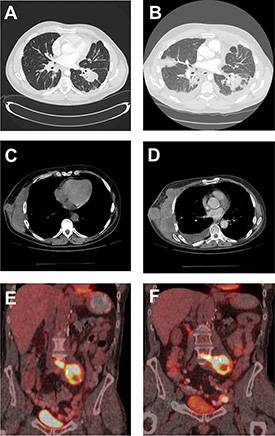

Clinical and demographic features of the patients in this study include the phenotype of their primary renal cell carcinoma, the metastatic site under treatment, and the type and duration of the rapalog therapy for the metastatic disease up to the time of progression and subsequent biopsy of the metastatic site, while on therapy (Table 1). Radiographic assessment, when applicable, confirmed the progressive nature of the metastatic disease in those patients on rapalog therapy and provided insight into the underlying conditions associated with such progression (Figure 1).

Figure 1: Radiographic imaging of baseline and progression of masses in RCC patients. CT of the chest of patient 3 demonstrating lung nodules at baseline (A) and progression of the disease with new lesions, lymphangitic spread and worsened left pleural effusion (B). CT of the chest of patient 7 demonstrating right chest wall mass at baseline (C) and subsequent progression of disease with increase in size of this target lesion (D). A PET-CT fused coronal image of patient 4 showing intensely FDG-avid retroperitoneal lymph nodal mass (SUV of 12.1) at baseline (E) and subsequent development of new left external iliac lymph node (SUV of 22) as well as mild increase in the FDG activity of the retroperitoneal lymph nodal mass (SUV of 14.8) (F).